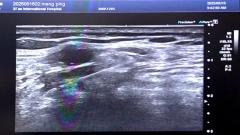

早高峰车祸重伤 西安国际医学中心医院多学科接力上演生死时速